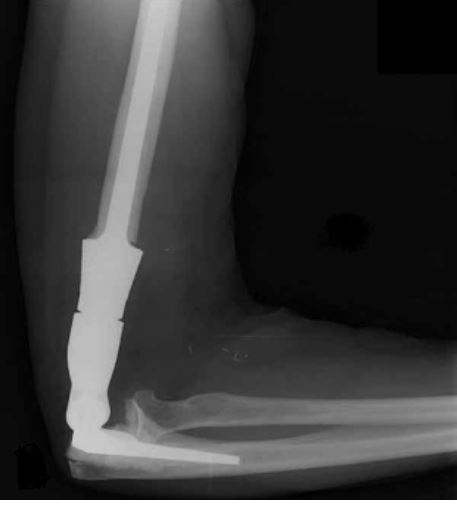

This is an X-ray image of the arm with the prosthesis.